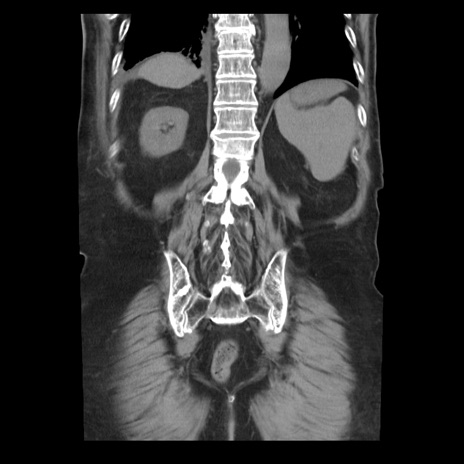

症例21(冠状断像)

【症例】70歳代男性

【主訴】腹痛

【現病歴】肝硬変・肝細胞癌にてかかりつけの方。約9時間前に食後より腹痛出現。症状が徐々に増悪し、嘔吐出現したため来院。

【既往歴】肝硬変、肝細胞癌(RFA、TACE後)

【身体所見】意識清明、表情苦悶様、BT 36℃、BP 129/78mmHg、P 88bpm、SpO2 97%(RA)、右上腹部から心窩部にかけて圧痛あり、反跳痛なし、筋性防御あり。

【データ】WBC 5800、CRP 0.16